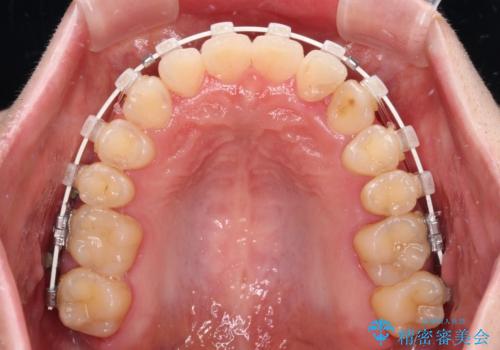

- 矯正装置

- 審美装置

マウスピース矯正は自己管理が煩わしいとのことで、ワイヤー装置にて矯正治療を行うこととしました。

思っていた以上に上顎歯列を後方に移動させることができ、すっきりとした口元に仕上げることができました。